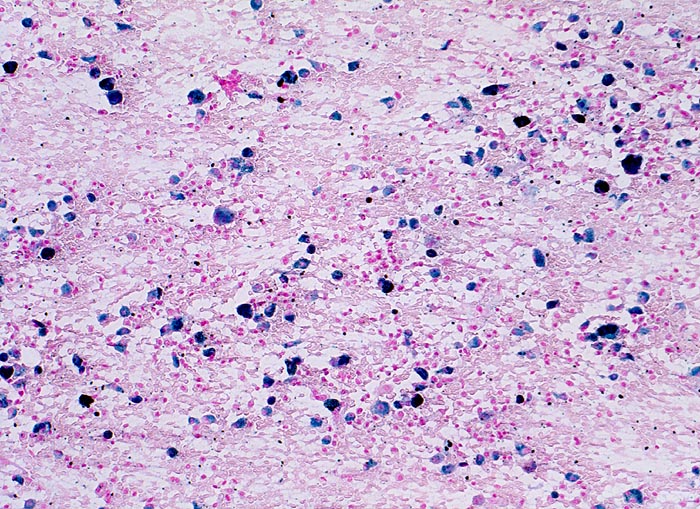

Herzfehlerzellen

vaskulär / Durchblutungsstörung

Lunge, Mediastinum mit Thymus

Sputum

Siderophagen lassen sich im Sputum nach intraalveolären Blutungen nachweisen. Intraalveoläre Blutungen infolge Linksherzinsuffizienz sind die häufigste Ursache. Andere Ursachen für intraalveoläre Blutungen sind Lungeninfarkte, eine toxische Kapillarschädigung, eine Vaskulitis oder Blutaspiration. Der Nachweis von Erythrozyten im Zytoplasma von Makrophagen spricht für eine frische Blutung. Hämosiderin wird nach 3-5 Tagen mit der Eisenfärbung nachweisbar. Als sicherer Hinweis auf eine ältere Blutung gelten >20% Siderophagen in der BAL.